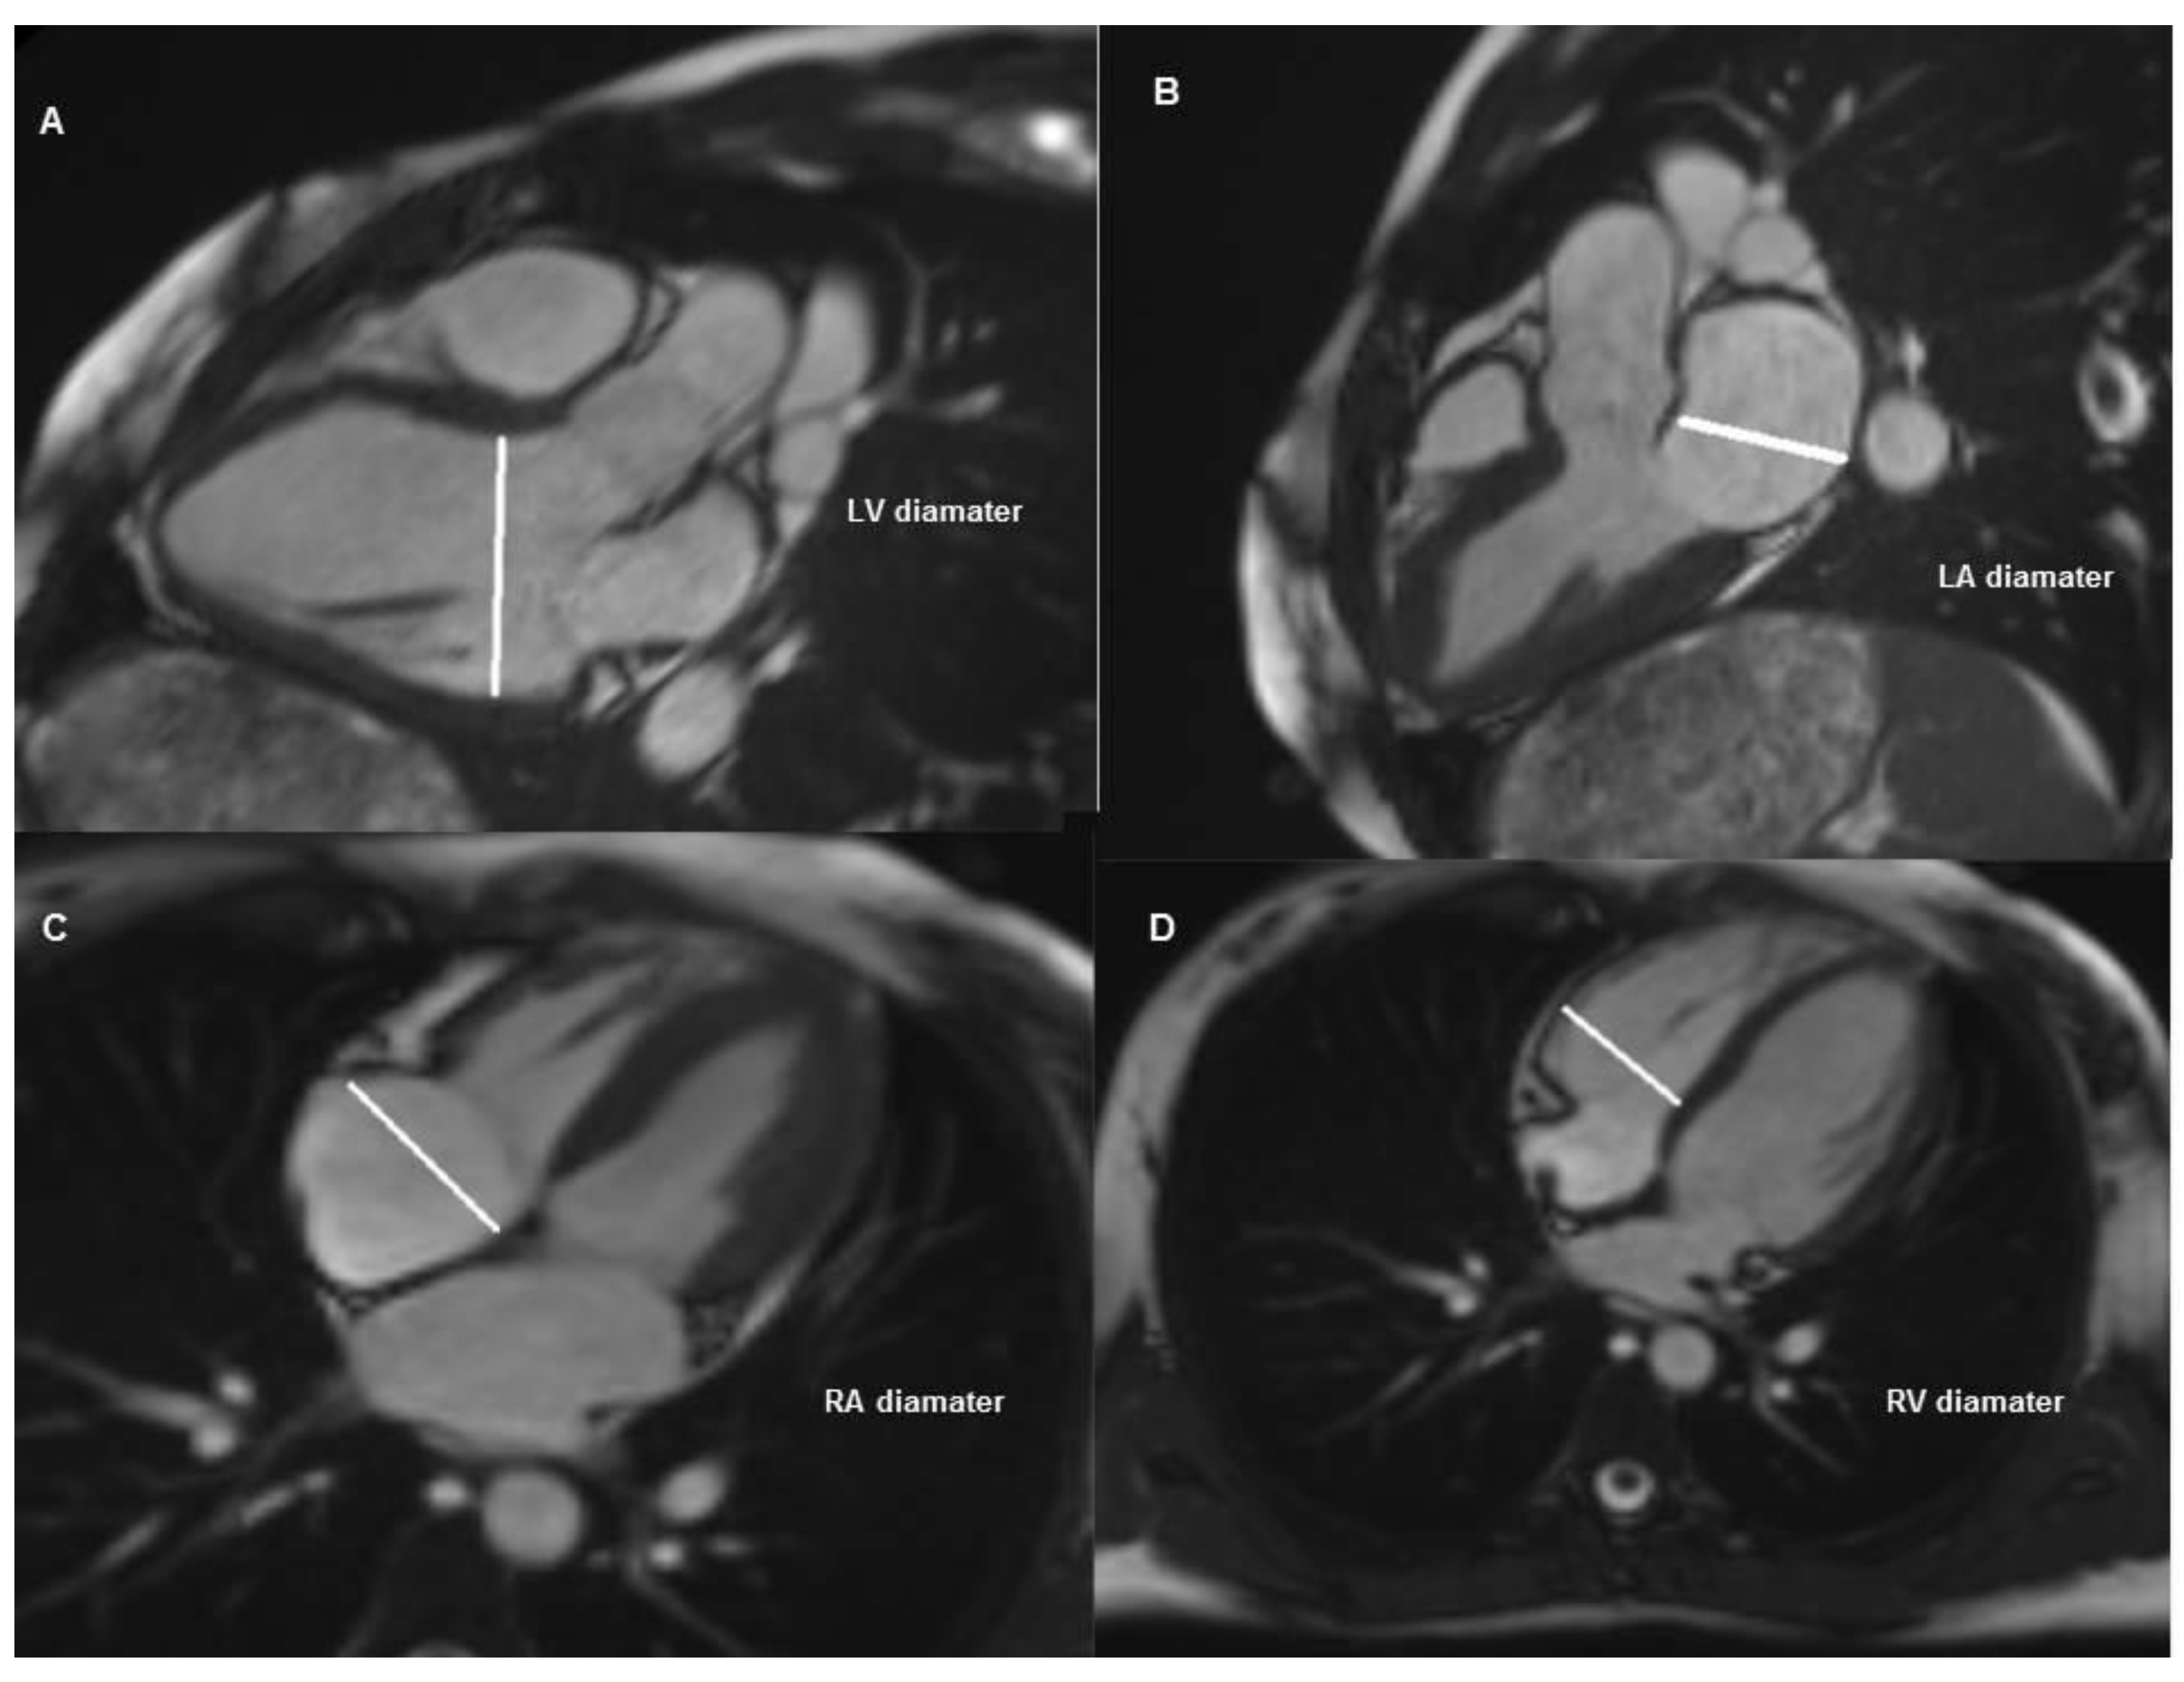

2. Materials and Methods

2.1. Subject Selection and Imaging Protocols